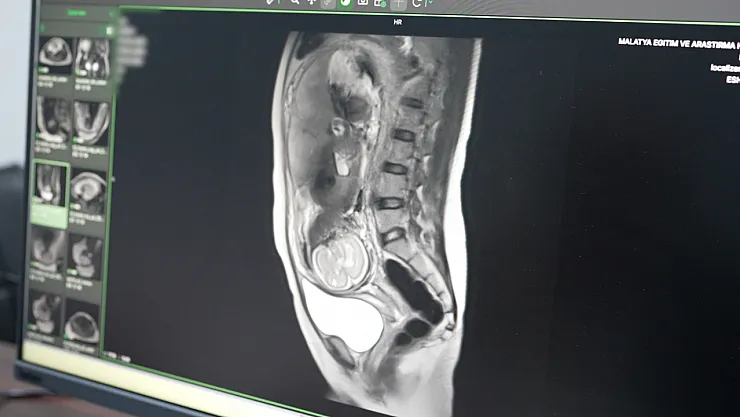

Hastanenin teknolojik atağı sadece kalp sağlığıyla sınırlı kalmadı. Daha önce yalnızca büyükşehirlerdeki tam teşekküllü merkezlerde yapılabilen "Multiparametrik Prostat MR" ve "Kardiyak MR" gibi özellikli işlemler artık Malatya’da rutin hale geldi. Özellikle anne adaylarını yakından ilgilendiren Fetal MR uygulamasıyla, anne karnındaki bebeklerin gelişimsel süreçleri ve olası anomalileri detaylıca incelenebiliyor. Bu yöntem, doğum öncesi planlamaların çok daha sağlıklı yapılmasına imkan tanıyor.